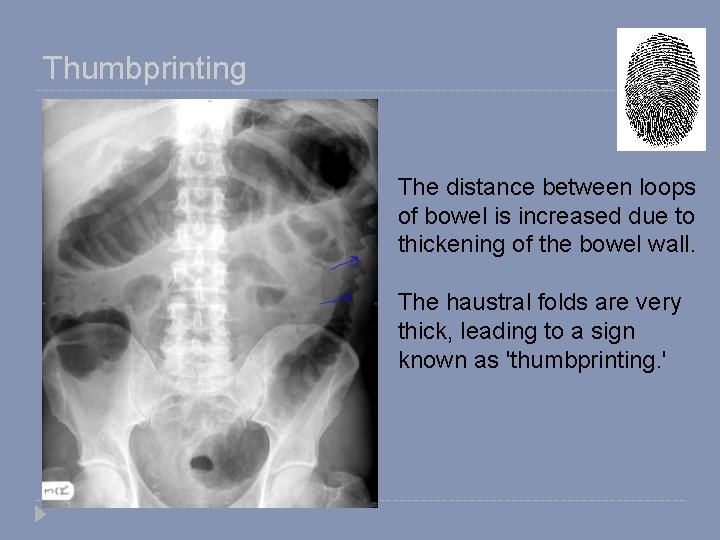

Thumbprinting The distance between loops of bowel is increased due to thickening of the bowel wall. The haustral folds are very thick, leading to a sign known as 'thumbprinting. '